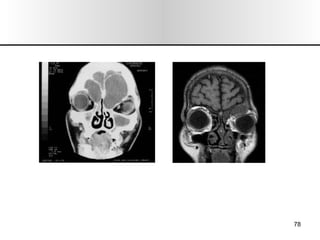

EXPLORACION 1.- Inspección/ Palpación:  Forma, color, alt. Dermicas, movilidad, dolor, inspiración forzada (colapso alar). 2.- Rinoscopia Ant: Desvios, esporones, cornetes, polipos  (solitario),  secreciones, perforaciones, CE, tumores. 3.- Rinoscopia Post: Hipertrofia cornetes, tumores. 4.- Tacto de Cavum: Adenoides. 5.- Rinonanometria: Dif de presión entre vestíbulo y coanas, flujo de vol. 6.- Exp. Radiológica : mentonasoplaca, frontonasoplaca, perfil, axial de Hirtz o submentovertex. TAC, RMN. 7.- Endoscopia Rinusinusal. 8.- Pruebas Alergologicas: pruebas cutaneas, eosinofilia, exudado nasal. SEMIOLOGIA

EXPLORACION 1.- Inspección/Palpación: Forma, color, alt. Dermicas, movilidad, dolor, inspiración forzada (colapso alar). 2.- Rinoscopia Ant: Desvios, esporones, cornetes, polipos (solitario), secreciones, perforaciones, CE, tumores. 3.- Rinoscopia Post: Hipertrofia cornetes, tumores. 4.- Tacto de Cavum: Adenoides. 5.- Rinonanometria: Dif de presión entre vestíbulo y coanas, flujo de vol. 6.- Exp. Radiológica : mentonasoplaca, frontonasoplaca, perfil, axial de Hirtz o submentovertex. TAC, RMN. 7.- Endoscopia Rinusinusal. 8.- Pruebas Alergologicas: pruebas cutaneas, eosinofilia, exudado nasal. SEMIOLOGIA